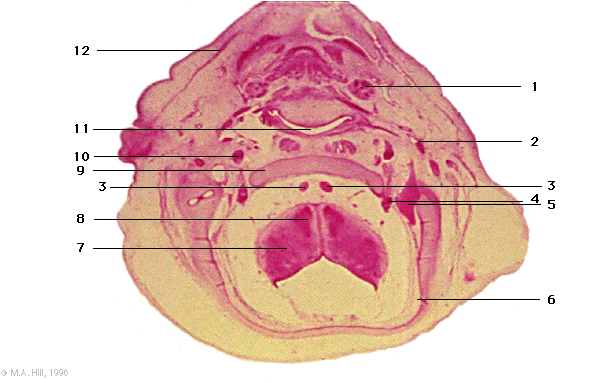

1 |

submandibular gland |

2 |

external carotid artery |

3 |

vertebral arteries |

4 |

vagus ganglion (X) |

5 |

internal jugular vein |

6 |

periotic capsule |

7 |

myelencephalon (medulla) |

8 |

inferior olive |

9 |

paracaudal plate |

10 |

internal carotid artery |

11 |

pharynx |

12 |

platysma muscle |